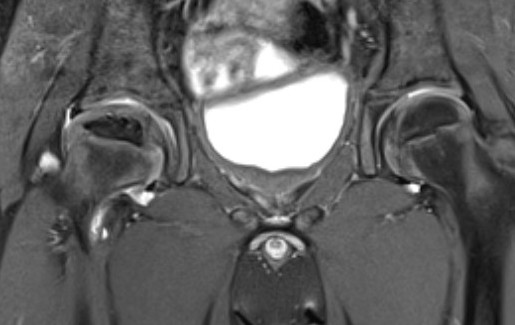

MRI

Advantage

- can assess amount of cartilaginous head outside of acetabulum

- very good way of assessing containment of cartilage head